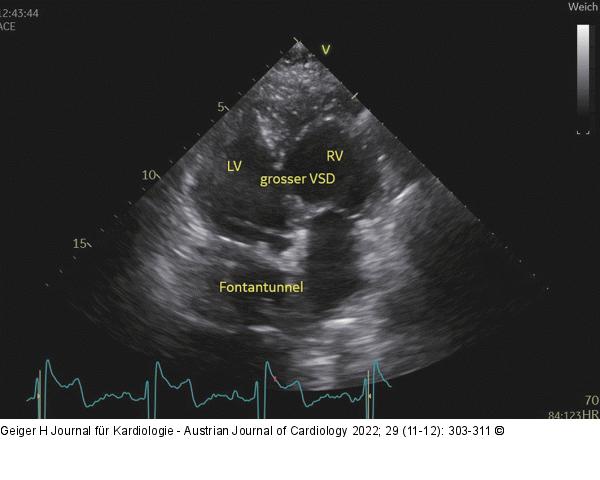

Abbildung 7: Fontan-Herz Fontan-Herz, Blick von apikal. Man sieht 2 Kammern, die durch einen großen VSD verbunden sind, so dass ein funktioneller Single Ventricle entsteht. Die Kammer, die da liegt, wo man den linken Ventrikel erwarten würde, also rechts, ist stark trabekuliert, apikal imponiert, das Moderatorband, die Klappenebene ist weit vorne, somit handelt es sich um den morphologisch rechten Ventrikel; die Kammern liegen also in Transpositionsstellung. Das Blut aus der Lunge gelangt (teilw. über einen ASD) in beide Vorhöfe, beide entleeren sich in die Ventrikel. Beide Ventrikel geben das Blut in die Aorta ab, da der Pulmonalishauptstamm und Aorta ascendens zusammengeleitet werden (nicht sichtbar). Es wird nur eine EF von 35–40 % benötigt, um ein ausreichendes Schlagvolumen zu erzeugen, was nicht beunruhigen sollte, da es normal ist. Das Blut aus der unteren Hohlvene wird im Fontan-Tunnel am Herzen vorbei direkt in die Lunge geleitet. Das Blut aus der oberen Hohlvene umgeht das Herz ebenfalls über die Glenn-Anastomose, die bei Erwachsenen aber selten direkt visualisierbar ist. |

Abbildung 7: Fontan-Herz